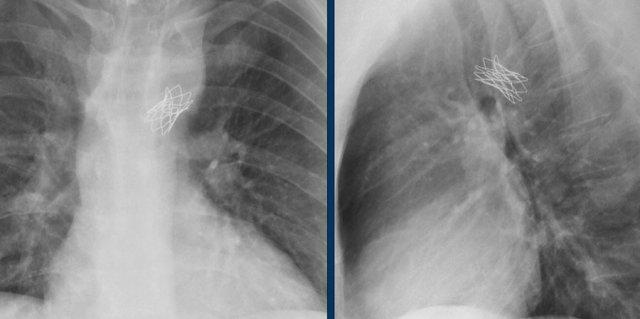

Hình ảnh chiếu bên của một trẻ em bị thông liên nhĩ với thiết bị bít lỗ thông Amplatz.

Hình ảnh chiếu bên của một trẻ em bị thông liên nhĩ với thiết bị bít lỗ thông dạng ô Rashkind.

Hình ảnh của một bệnh nhân bị thông liên nhĩ với thiết bị bít lỗ thông Amplatz.

Đây là bệnh nhân có lỗ thông lớn hơn, được bít bằng hai thiết bị.